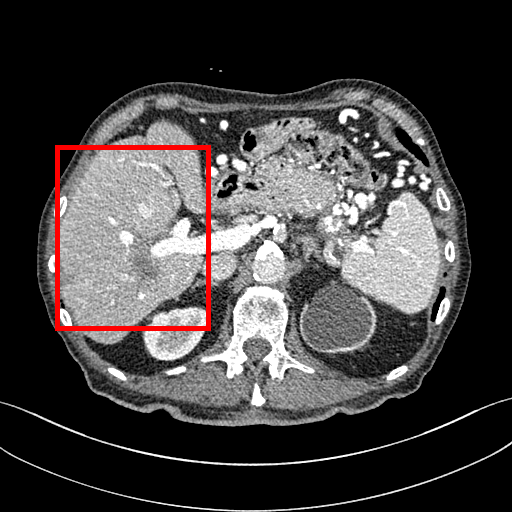

To demonstrate the effectiveness of the proposed network, we perform the qualitative comparisons over three representative abdominal images presented in Figs. 3, 5 and 7. For better evaluations of the image quality with different denoising models, zoomed regions-of-interest (ROIs) are marked by red rectangles and shown in Figs. 4, 6 and 8 respectively. Note that all results from different denoising models focus on two aspects: content restoration and noise-reduction. All CT images in axial view are displayed in the angiography window [-160, 240]HU.

The real NDCT images and corresponding LDCT images are presented in Figs. 3a and 3b. As observed, there are distinctions between ground truth (NDCT) images and LDCT images. Figs. 3a and 7a show the lesions/metastasis. Fig. 5a presents focal fatty sparing/focal fat. In Figs. 4a, 6a and 8a, these lesions can be clearly observed in NDCT images; in contrast, from Figs. 4b, 6b, and 8b, it can be seen that the original LDCT image is noisy, and lacks structural features for task-based clinical diagnosis. All adopted denoising models suppress noise to some extent.